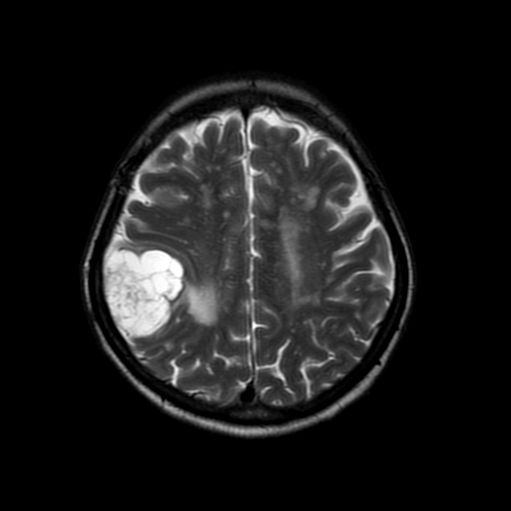

脳動静脈奇形

摘出術

南田/野本/元永